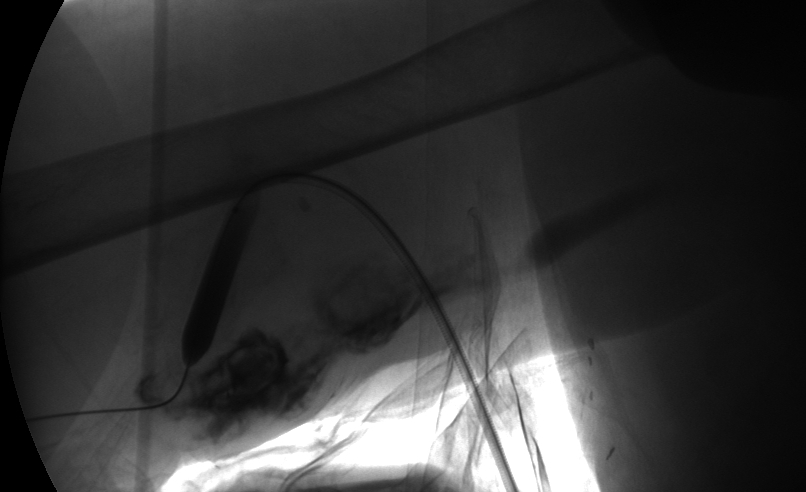

Dilating proximal and mid stenoses

Image during intervention: angioplasty of 1st and 2nd stenoses.